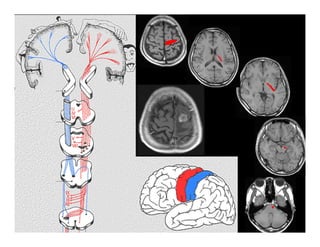

Chấn thương sọ não

Đậm độ cao/ Xuất huyết não

Đậm độ thấp/ Phù-dập não

GIẢI PHẪU HÌNH ẢNH

SỌ NÃO

Giải phẫu hình ảnh sọ não

(1): Bao trong

(2): Đầu nhân đuôi

(3): Nhân bèo

(4): Đồi thị

(5): Não thất III

(6): Sừng trán não